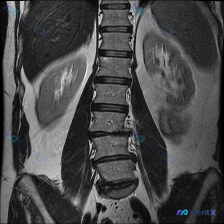

看到一张腹部MRI发现了脊柱侧弯,肾盂肾盏高信号是生理性还是病理性?

整理到一张腹部冠状位T2WI的影像资料: 首先一眼能看到脊柱侧弯,同时双侧肾盂、肾盏区域是明显的T2高信号。 原影像分析里第一反应偏“生理性尿液积聚”,但结合脊柱侧弯这个背景总觉得有点不踏实——毕竟侧弯可能导致输尿管扭曲或压迫,会不会是早期或轻度的梗阻性改变只是还没到典型“杯口变钝、肾盂明显扩张”的...